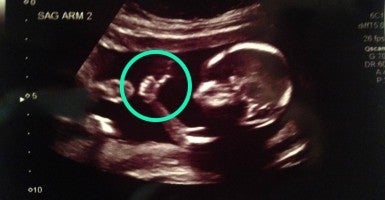

Reddit user “meancloth” shared this ultrasound photo of his twins yesterday. Apparently, one of these kids is already just a little bit of a show-off.